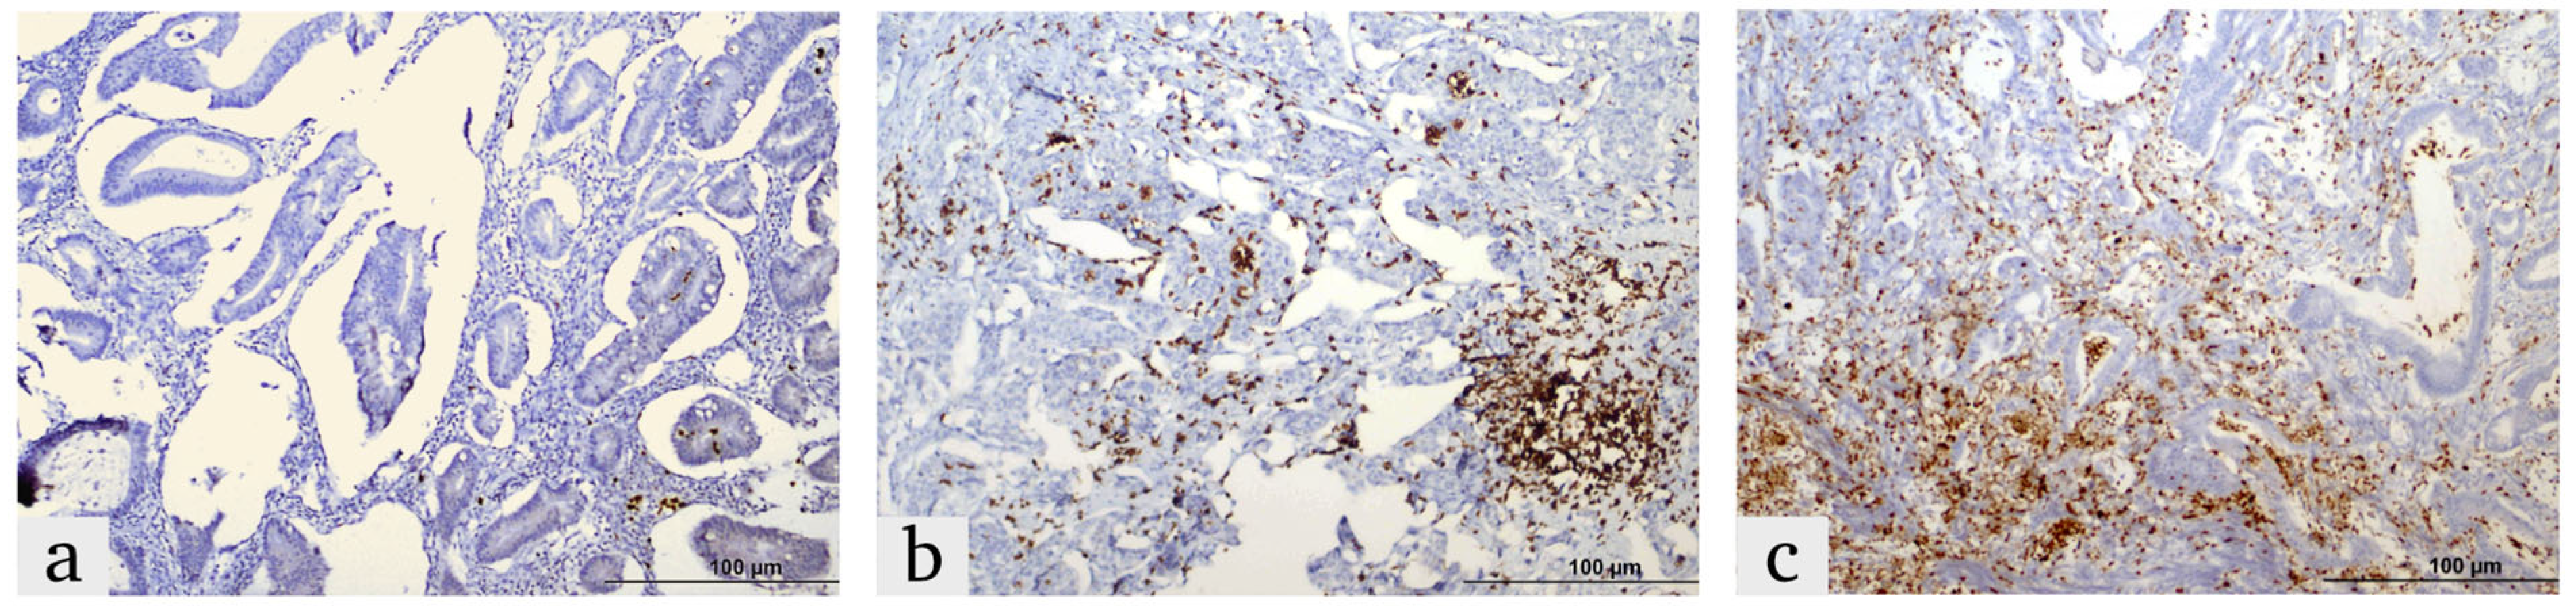

2.2. Immunohistochemistry (IHC) Procedure

2.3. IHC Score

- 0 (0%), 1 (0–25%), 2 (25–50%), 3 (50–75%) and 4 (75–100%).